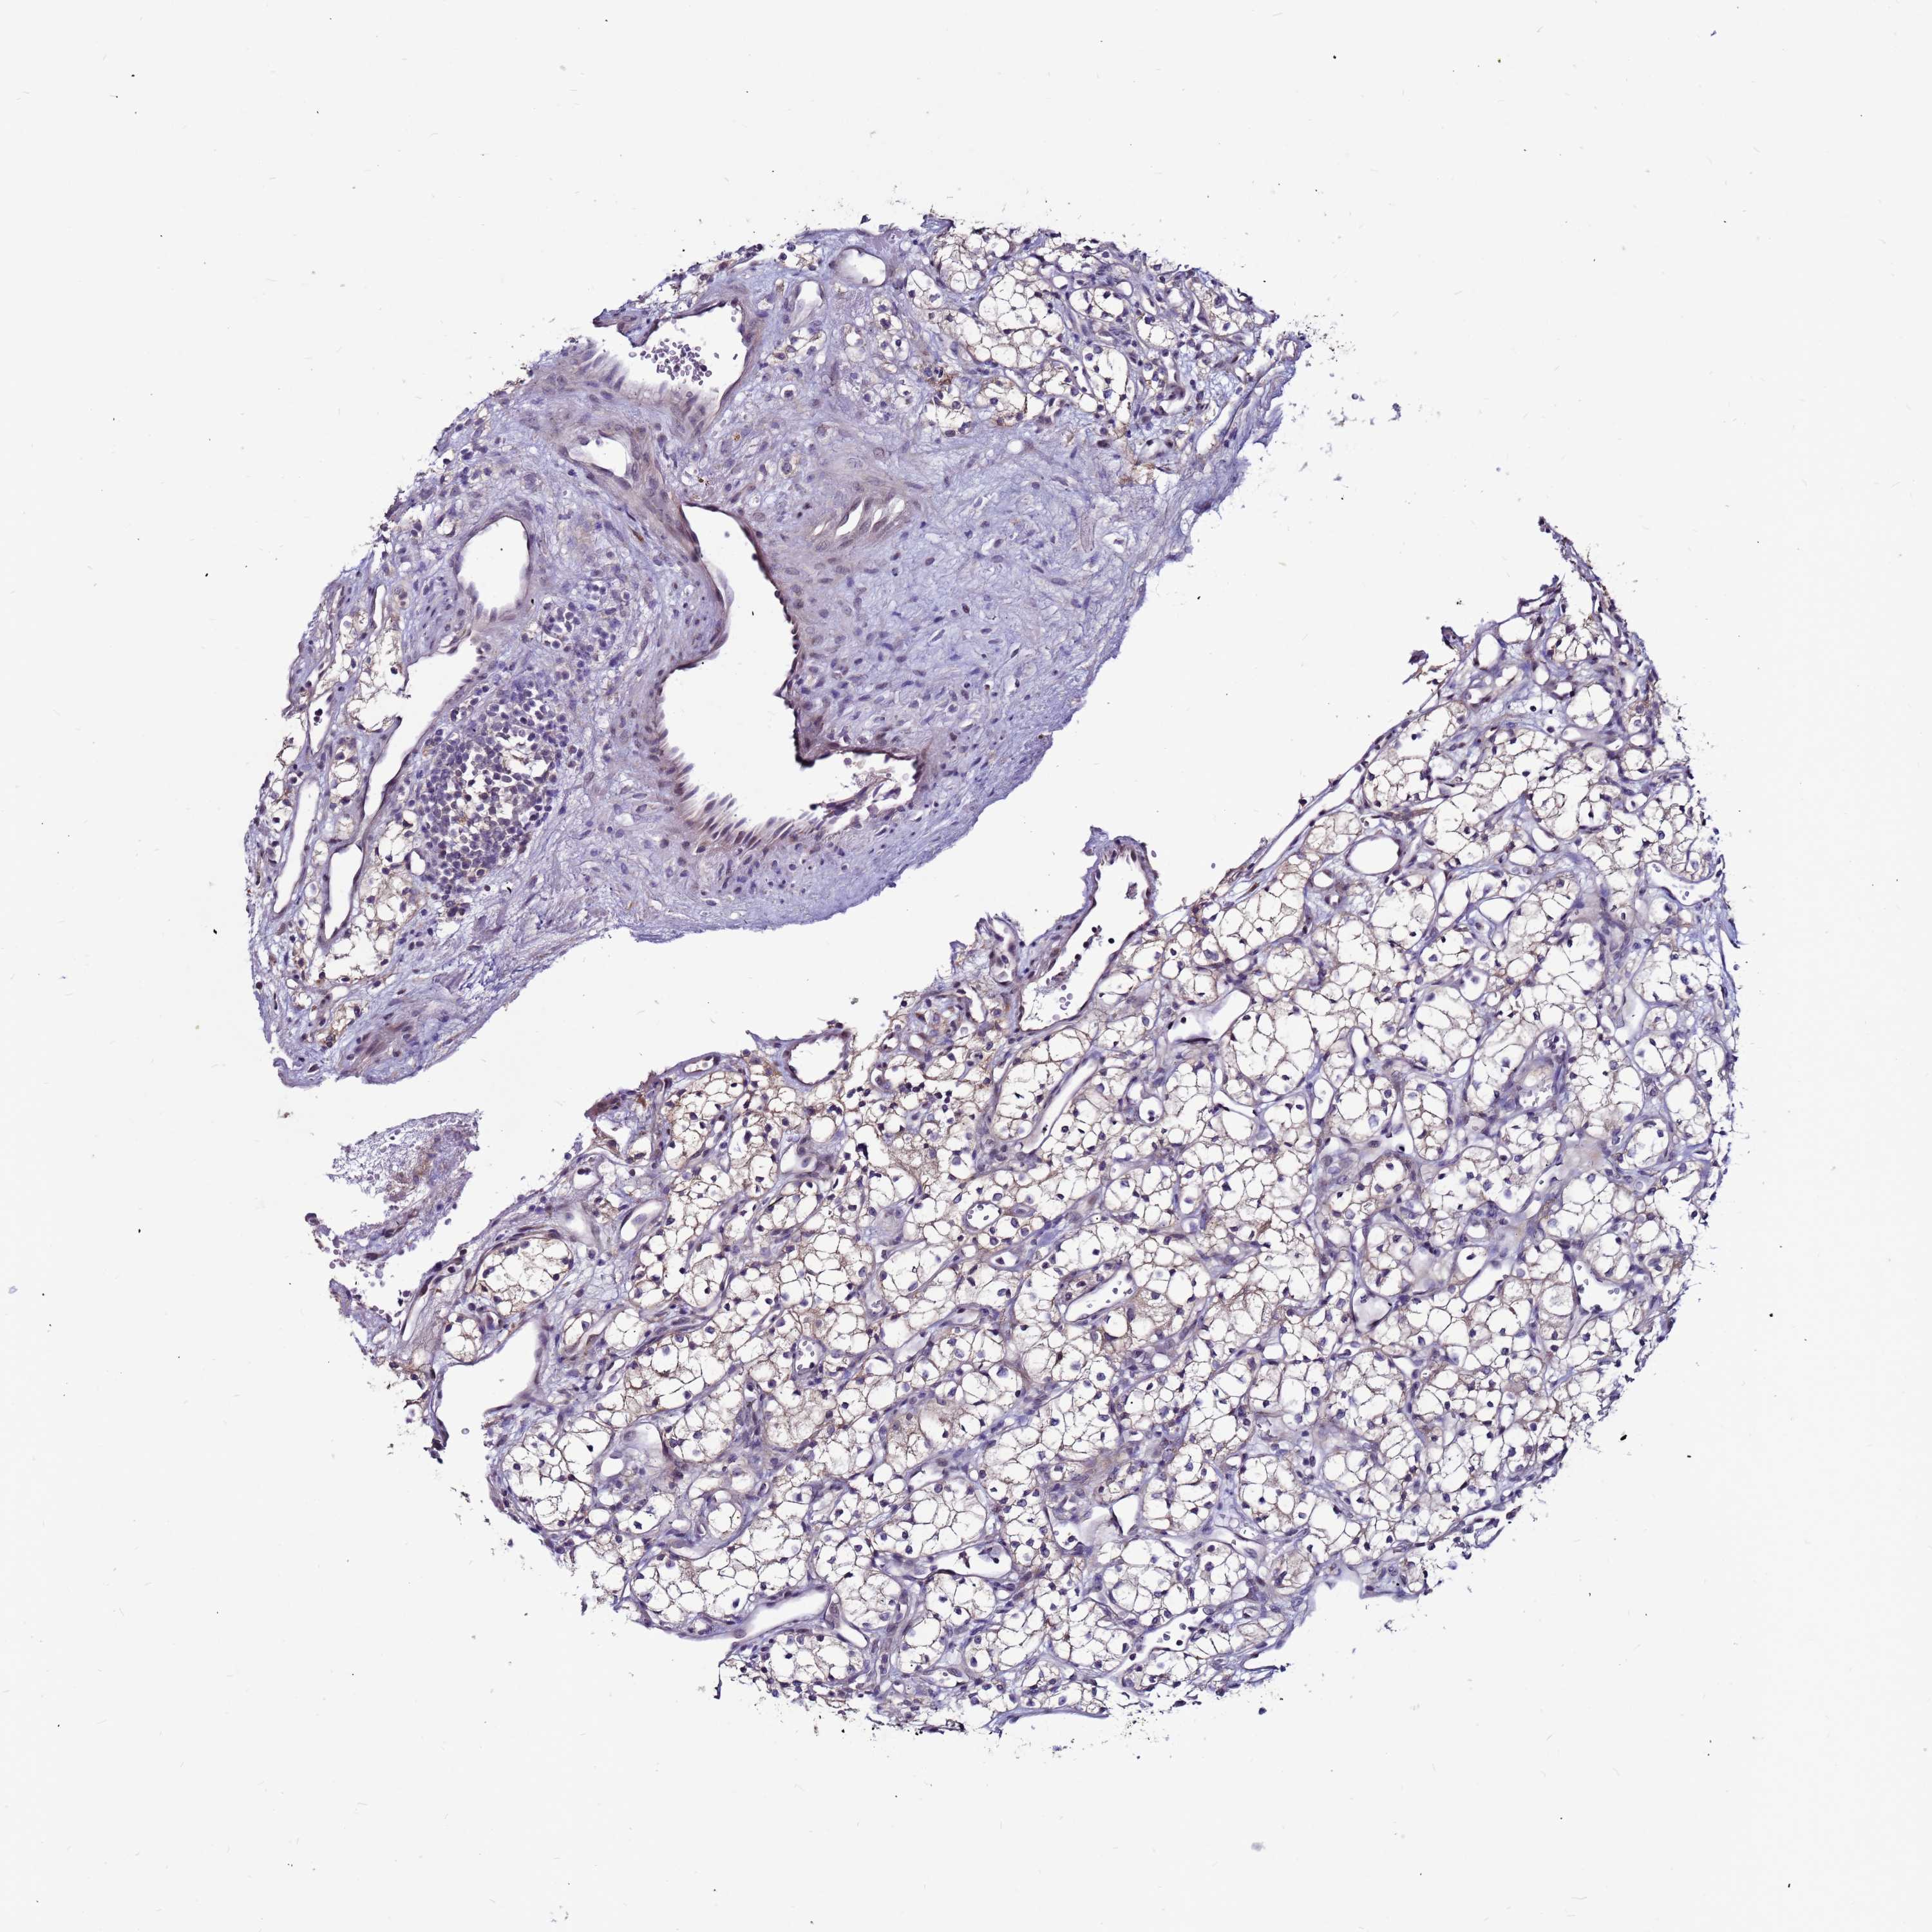

KIDNEY RENAL PAPILLARY CELL CARCINOMA (TCGA) - Interactive survival scatter ploti

The Survival Scatter plot shows the clinical status (i.e. dead or alive) for all individuals in the patient cohort, based on the same data that underlies the corresponding Kaplan-Meier plots. Patients that are alive at last time for follow-up are shown in blue and patients who have died during the study are shown in red.

The x-axis shows the expression levels (FPKM) of the investigated gene in the tumor tissue at the time of diagnosis. The y-axis shows the follow-up time after diagnosis (years). Both axes are complimented with kernel density curves demonstrating the data density over the axes. The top density plot shows the expression levels (FPKM) distribution among dead (red) and alive patients (blue). The right density plot shows the data density of the survived years of dead patients with high and low expression levels respectively, stratified using the cutoff indicated by the vertical dashed line through the Survival Scatter plot. This cutoff is automatically defined based on the FPKM cutoff that minimizes the p-score. The cutoff can be changed by dragging the vertical line or by entering a cutoff value in the square labeled "Current cut-off".

Under the Survival Scatter plot the p-score landscape (black curve; left axis) is shown together with dead median separation (red curve; right axis). Dead median separation is the difference in median mRNA expression between patients who have died with high and low expression, respectively. It is calculated as follows: median FPKM expression of dead patients with high expression - median FPKM expression of dead patients with low expression. This is intended to aid the user in visually exploring custom cutoffs and the associated p-scores and dead median separation.

Individual patient data is displayed and can be filtered by clicking on one or more of the category buttons on the top of the page. Categories describing expression level and patient information include: high, low, alive, dead, female, male and tumor stages. The scale of the x-axis can be toggled between linear and log-scale by clicking on the "x log" button. Mouse-over function shows TCGA ID, patient information and mRNA expression (FPKM) for each patient.

& Survival analysisi

Kaplan-Meier plots summarize results from analysis of correlation between mRNA expression level and patient survival. Patients were divided based on level of expression into one of the two groups "low" (under cut off) or "high" (over cut off). X-axis shows time for survival (years) and y-axis shows the probability of survival, where 1.0 corresponds to 100 percent.

SLC44A3 is not prognostic in Kidney Renal Papillary Cell Carcinoma (TCGA)